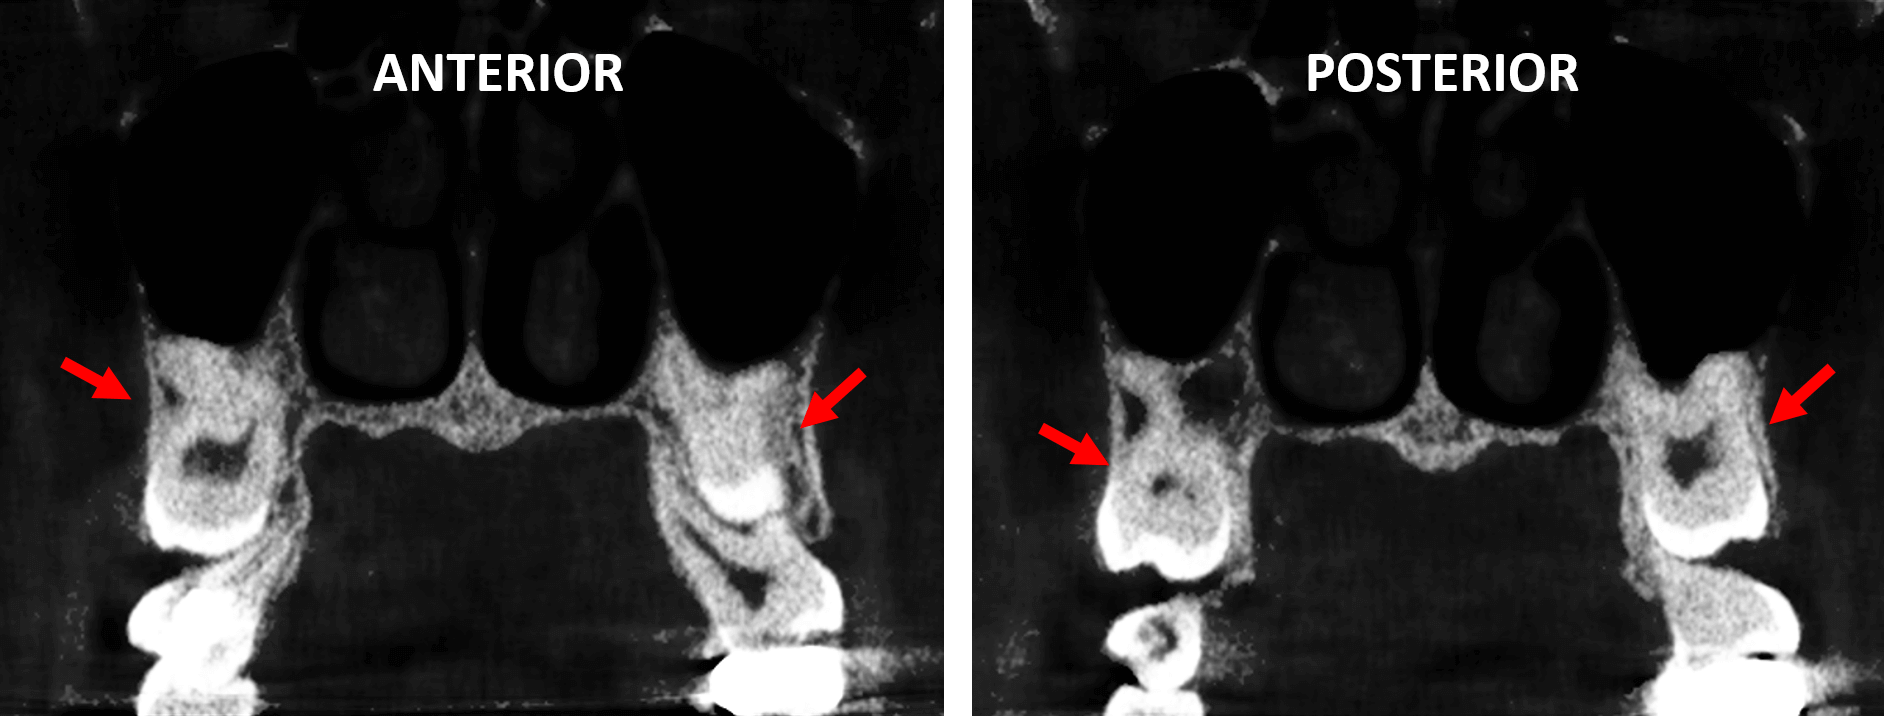

En la evaluación con tomografía del maxilar superior, se realizó la reconstrucción panorámica (Fig.1) donde se observan los órganos dentaros 18 y 28 (flechas rojas) retenidos en posición vertical impactados contra los órganos dentario 17 y 27. Nótese el tratamiento de conducto en el órgano dentario 17.

En cortes coronales (Fig.4) se observan de forma bilateral la impactacion bilateral de los terceros molares superoriores, con la corona parcialmente erupcionada y las raíces en estrecha relación con el piso del seno maxilar.